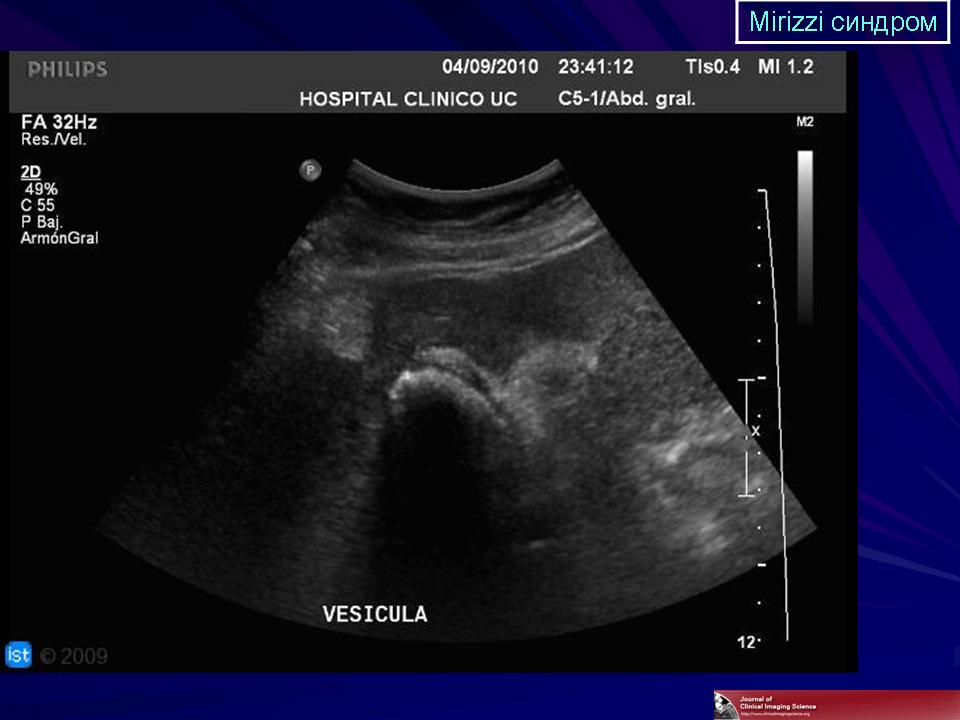

Все больные повергались общеклиническому обследованию, проводилось эндоскопическое исследование верхних отделов желудочно-кишечного тракта. УЗИ желчного пузыря, внутри- и внепеченочных желчных протоков, печени и её ворот, поджелудочной железы, а также желудка и двенадцатиперстной кишки производили с использованием аппарата Philips HDI 4000, в режиме реального времени. Использовали линейные и секторальные датчики с частотой 3,5 Мгц, а также допплеровский и энергетический датчики.

Результаты исследования и их обсуждение. Оценивая результаты УЗИ, которое было выполнено до операции, следует отметить, что использование новейшего ультразвукового сканера Philips HDI 4000 позволило у 89 (67,4%) пациентов установить диагноз синдром Мириззи. При оценке эхограмм нами придавалось значение размерам и расположению конкремента в желчном пузыре, интимному прилеганию гартмановского кармана с расположенным в нем конкрементом к правому либо общему печеночным протокам, признакам сдавления конкрементом общего желчного протока, наличию расширения внутри- и внепеченочных желчных протоков (рис.1,2). При оценке результатов ЭРХПГ патогномоничным для синдром Мириззи считали характерное сдавление извне общего желчного протока, либо наличие холецистохоледохеального свища, что было установлено у 77 (58,3%) больных.